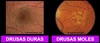

Como podemos classificar as drusas?

Drusas Duras

- drusas pequenas (<63micrometros), bem delimitadas

- comum após os 50 anos

- baixo risco para DMRI

Drusas Moles

- drusas grandes, mal delimitadas

- confluentes

- Alto risco para formas graves de DMRI (13%)

* se associada com alteração pigmentar (50%)